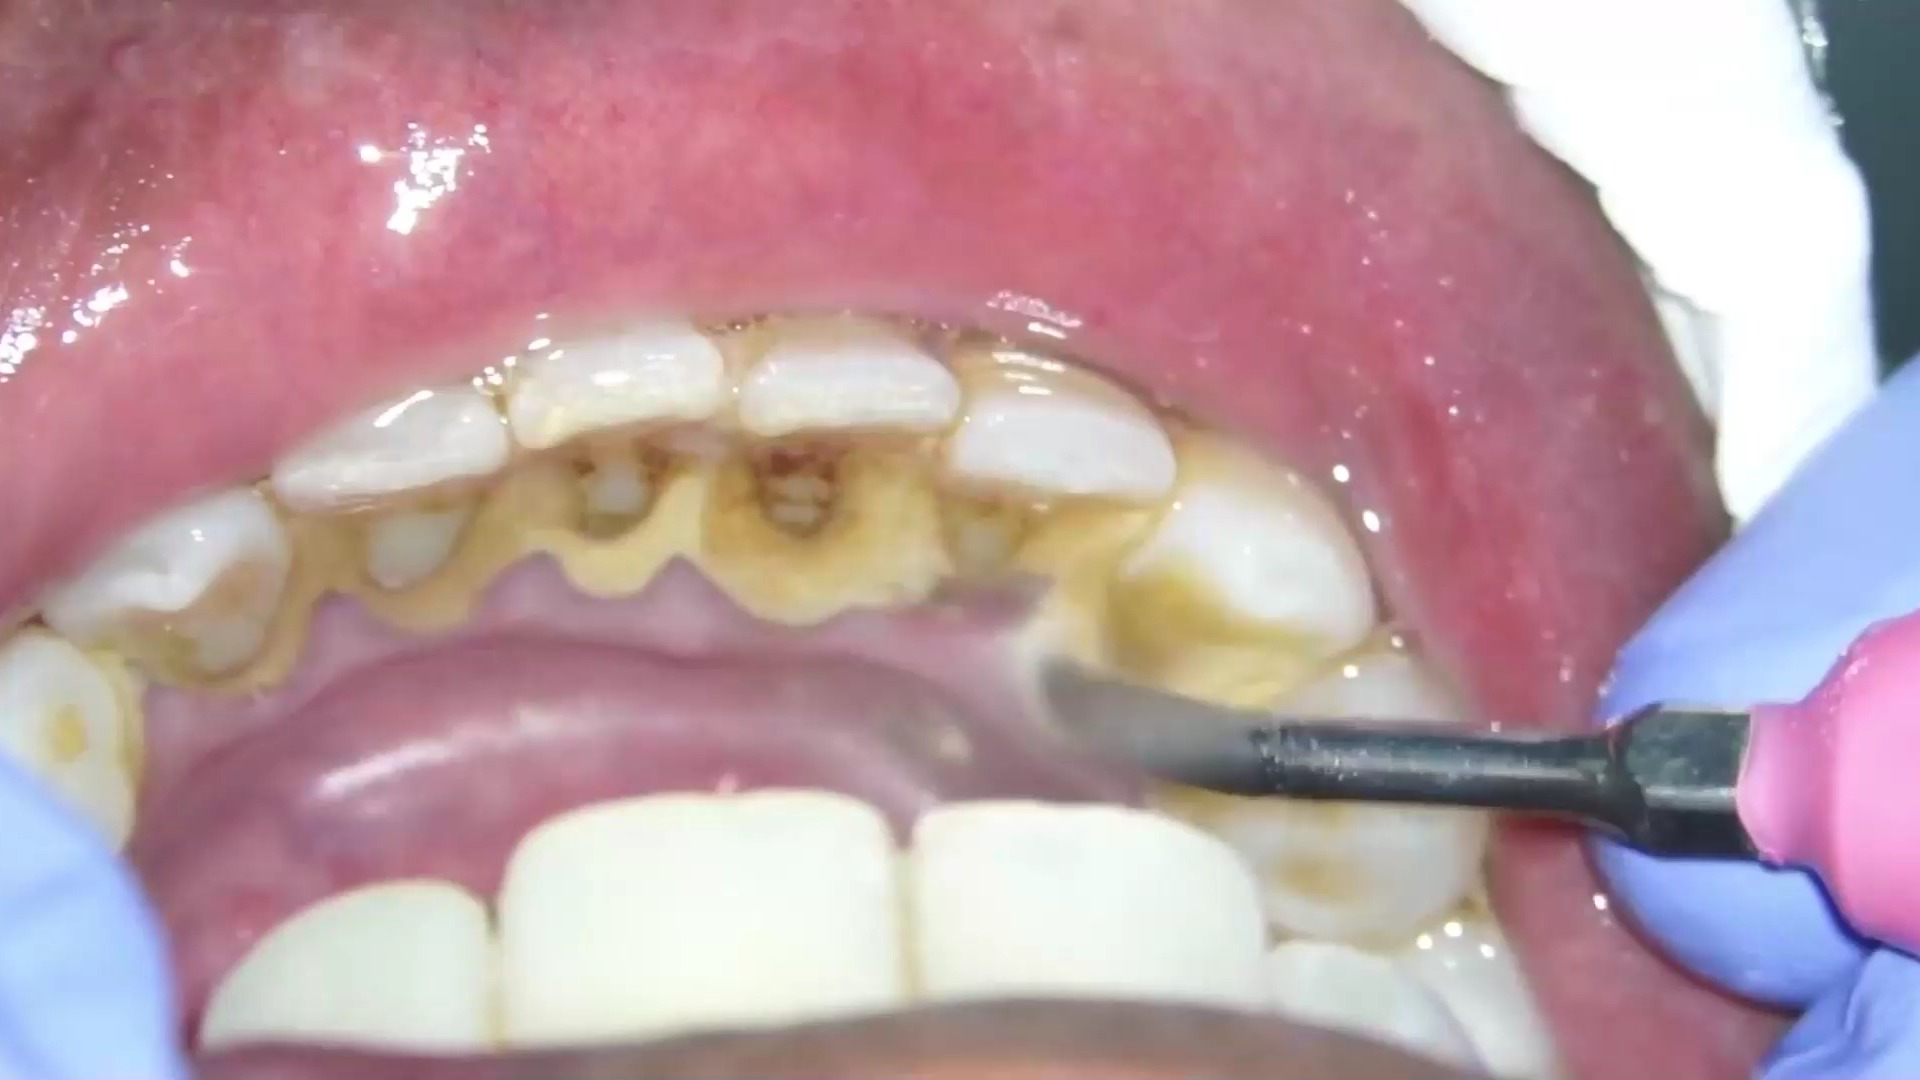

牙齿缝隙发黑不一定是蛀牙,也可能是其他情况,具体如下1 蛀牙的可能性蛀牙龋齿是细菌分解食物残渣产生酸性物质,腐蚀牙釉质和牙本质导致的若牙缝发黑且伴随牙齿敏感疼痛或洞状缺损,可能是蛀牙的早期或进展期表现此时需通过口腔检查和X光片确认龋坏深度,尽早补牙以防止龋坏扩大,避免牙齿结构;3 牙髓坏死根管治疗当牙髓因感染或外伤死亡时,牙齿可能变色灰黑或黄褐根管治疗需清除坏死牙髓,消毒根管后填充,防止感染扩散至根尖周组织治疗完成后通常需做牙冠保护剩余牙体4 色素沉着牙齿美白外源性色素如咖啡茶烟渍或内源性色素如四环素牙可能导致牙缝发黑化学美白;牙齿咬合面上缝隙发黑主要有两种情况第一色素沉着第二龋齿如果是色素沉着,用探针探入黑色的区域是不能够探进去的,表面是硬的,不需要进行任何处理,只是单纯的色素沉着如果是龋齿,用探针是可以探入,并且有勾拉感,能够阻止探针的滑动,就是明显的龋齿,需要将腐质以及黑色区域全部磨除。

牙齿缝隙发黑有可能是牙结石或者是烟渍茶渍等色素沉积,这种情况可以通过超声波洁牙的方式,将牙齿缝隙处黑色物质去除超声波洁牙是利用高频震荡超声波,将牙齿表面的牙结石去除,并不会对牙齿本身造成伤害,整个过程也比较快捷,大概只需要一个小时左右的时间,而且洗牙后医生会对患者的牙齿进行全面的抛光;牙齿咬合面上缝隙发黑通常是出现了龋齿具体原因和影响如下龋齿形成机制牙齿咬合面的缝隙因形态复杂,易残留食物残渣并滋生细菌在适宜环境下,细菌代谢产生酸性物质,逐渐侵蚀牙齿硬组织牙釉质牙本质,导致矿物质流失脱矿,最终形成龋洞缝隙处清洁难度大,成为龋齿高发区域发展过程与危害;牙齿缝隙有黑的抠不下来,可能是以下原因蛀牙由于牙齿缝隙的特殊解剖结构,普通刷牙漱口等清洁方法难以有效清洁缝隙细菌在缝隙中生长,腐蚀牙面,形成龋洞,即发黑部分时间久了,龋洞变大,肉眼可看到牙缝里发黑色素沉着部分饮食因素是造成牙齿色素沉着的主要原因如果没有形成定期洗牙的习惯。